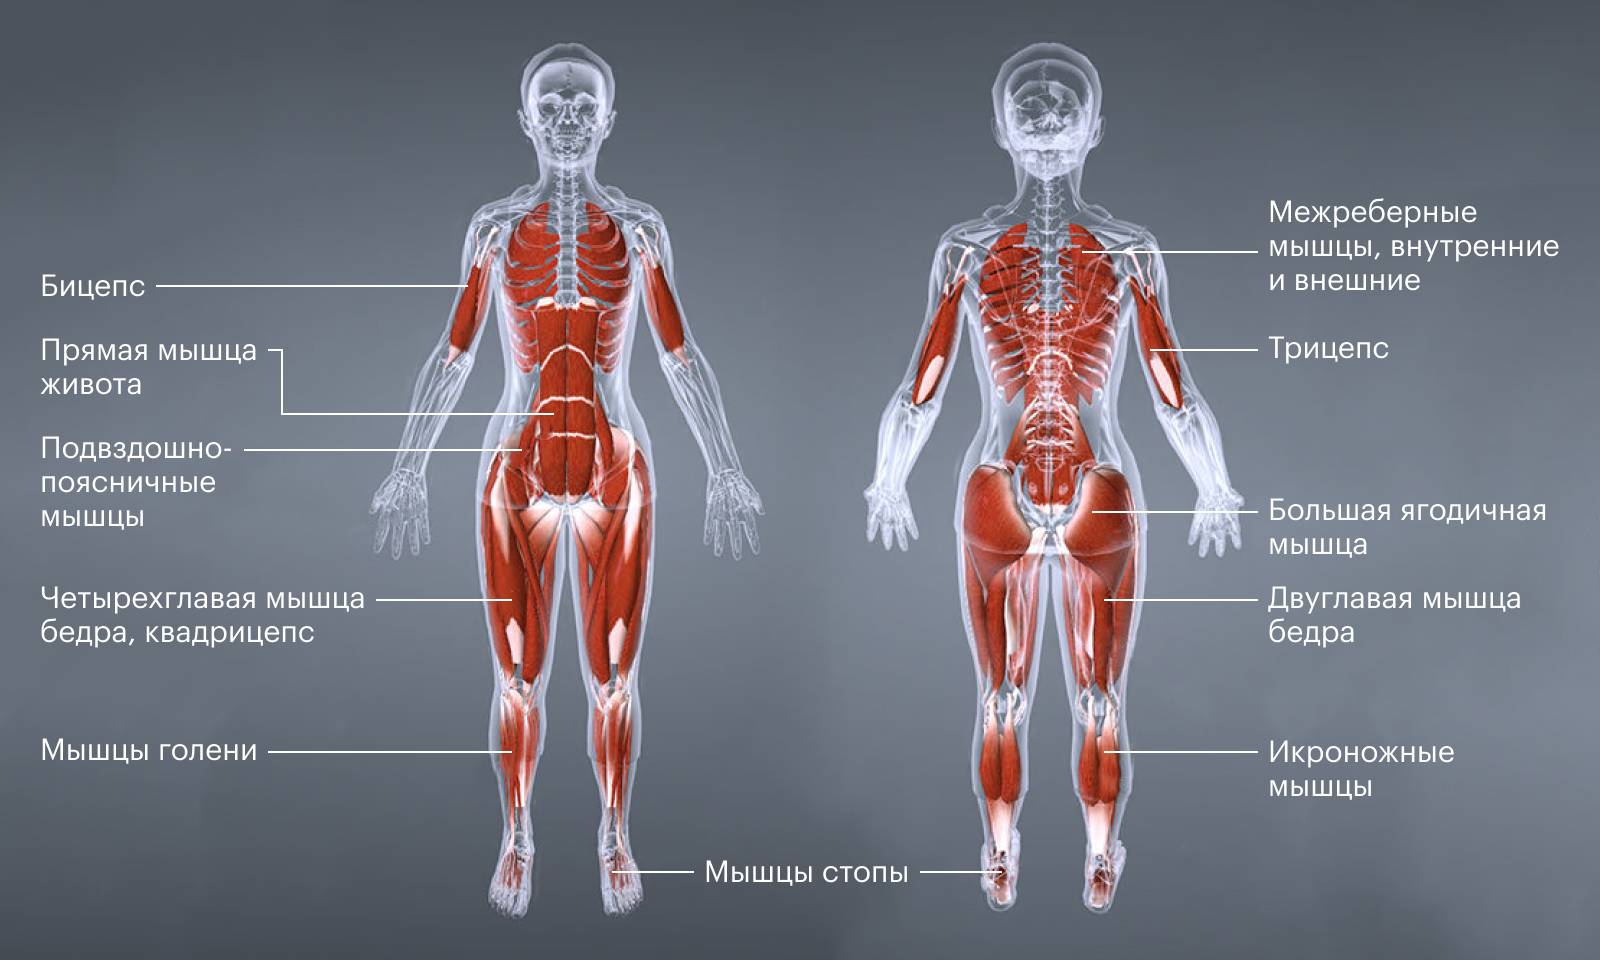

Свойства мышц человека: Основные характеристики

Раздел: Объективный взгляд